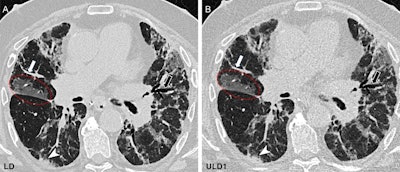

Chest CT in the craniocaudal direction at inspiration in a 62-year-old male participant with a combination of obstructive and restrictive chronic lung allograft dysfunction one year after lung transplant due to fibrosis. (A) Standard-of-care low-dose (LD) image (effective dose, 1.77 mSv) and (B) ultralow-dose (ULD1) image (effective dose, 0.307 mSv) show a comparison of image quality between protocols. Peripheral vessels (white arrows), bronchiectasis (black arrows), ground-glass opacity (red circles), and small consolidations (arrowheads) seen on the LD image (A) have excellent visualization on the ULD1 image (B), which was acquired with a target effective dose of approximately 20% of the LD protocol. The subjective image quality scores of the ULD1 image were 4, 4, and 3.Image and caption courtesy of the RSNA